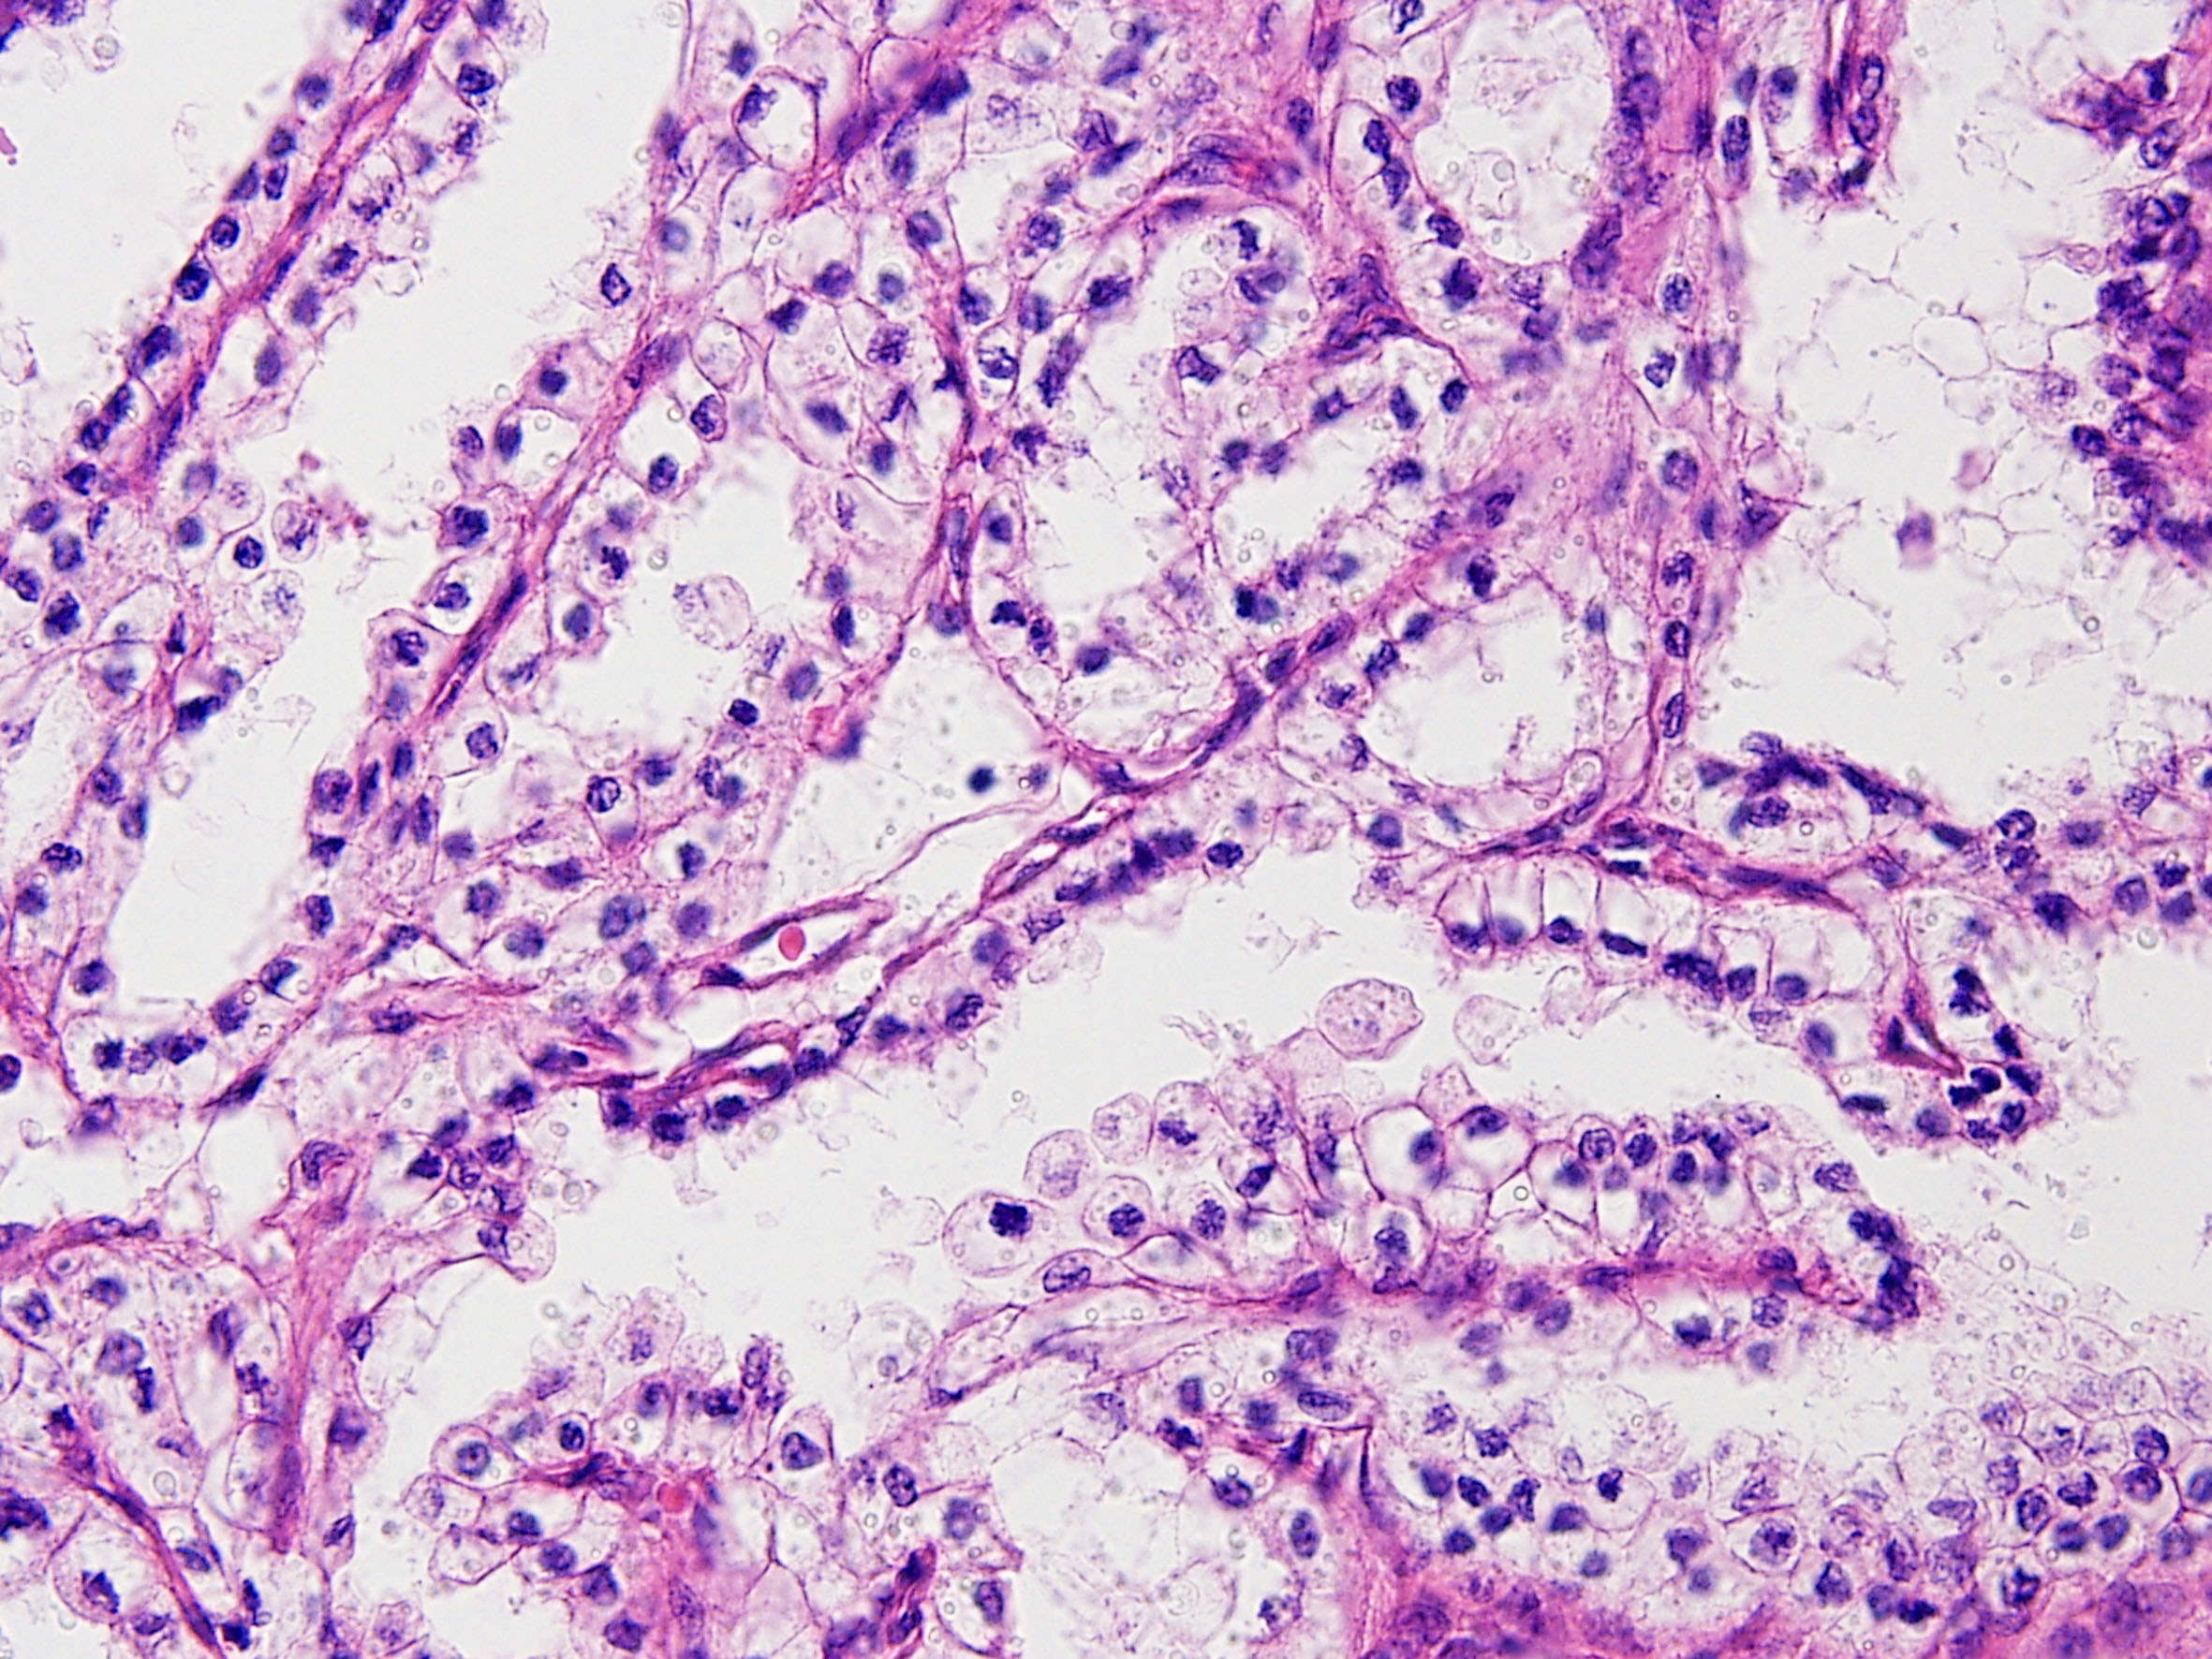

Classification of renal tumors

Case ID: 164